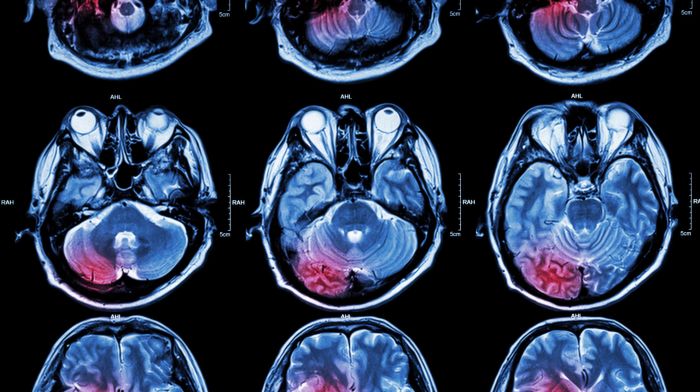

Чрезмерное употребление алкоголя связали с развитием ранних и тяжелых инсультов

Кровоизлияния в головной мозг происходили на 11 лет раньше